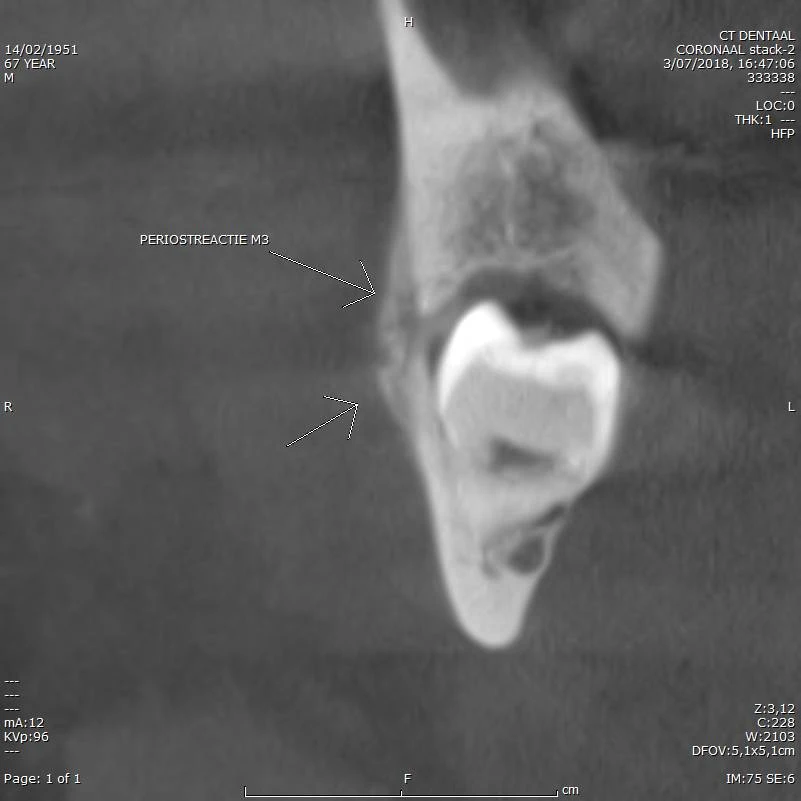

CBCT voorbeeld 4: periostreactie M3

Coronale doorsnede: periostreactie M3, botdoorbraak buccaal